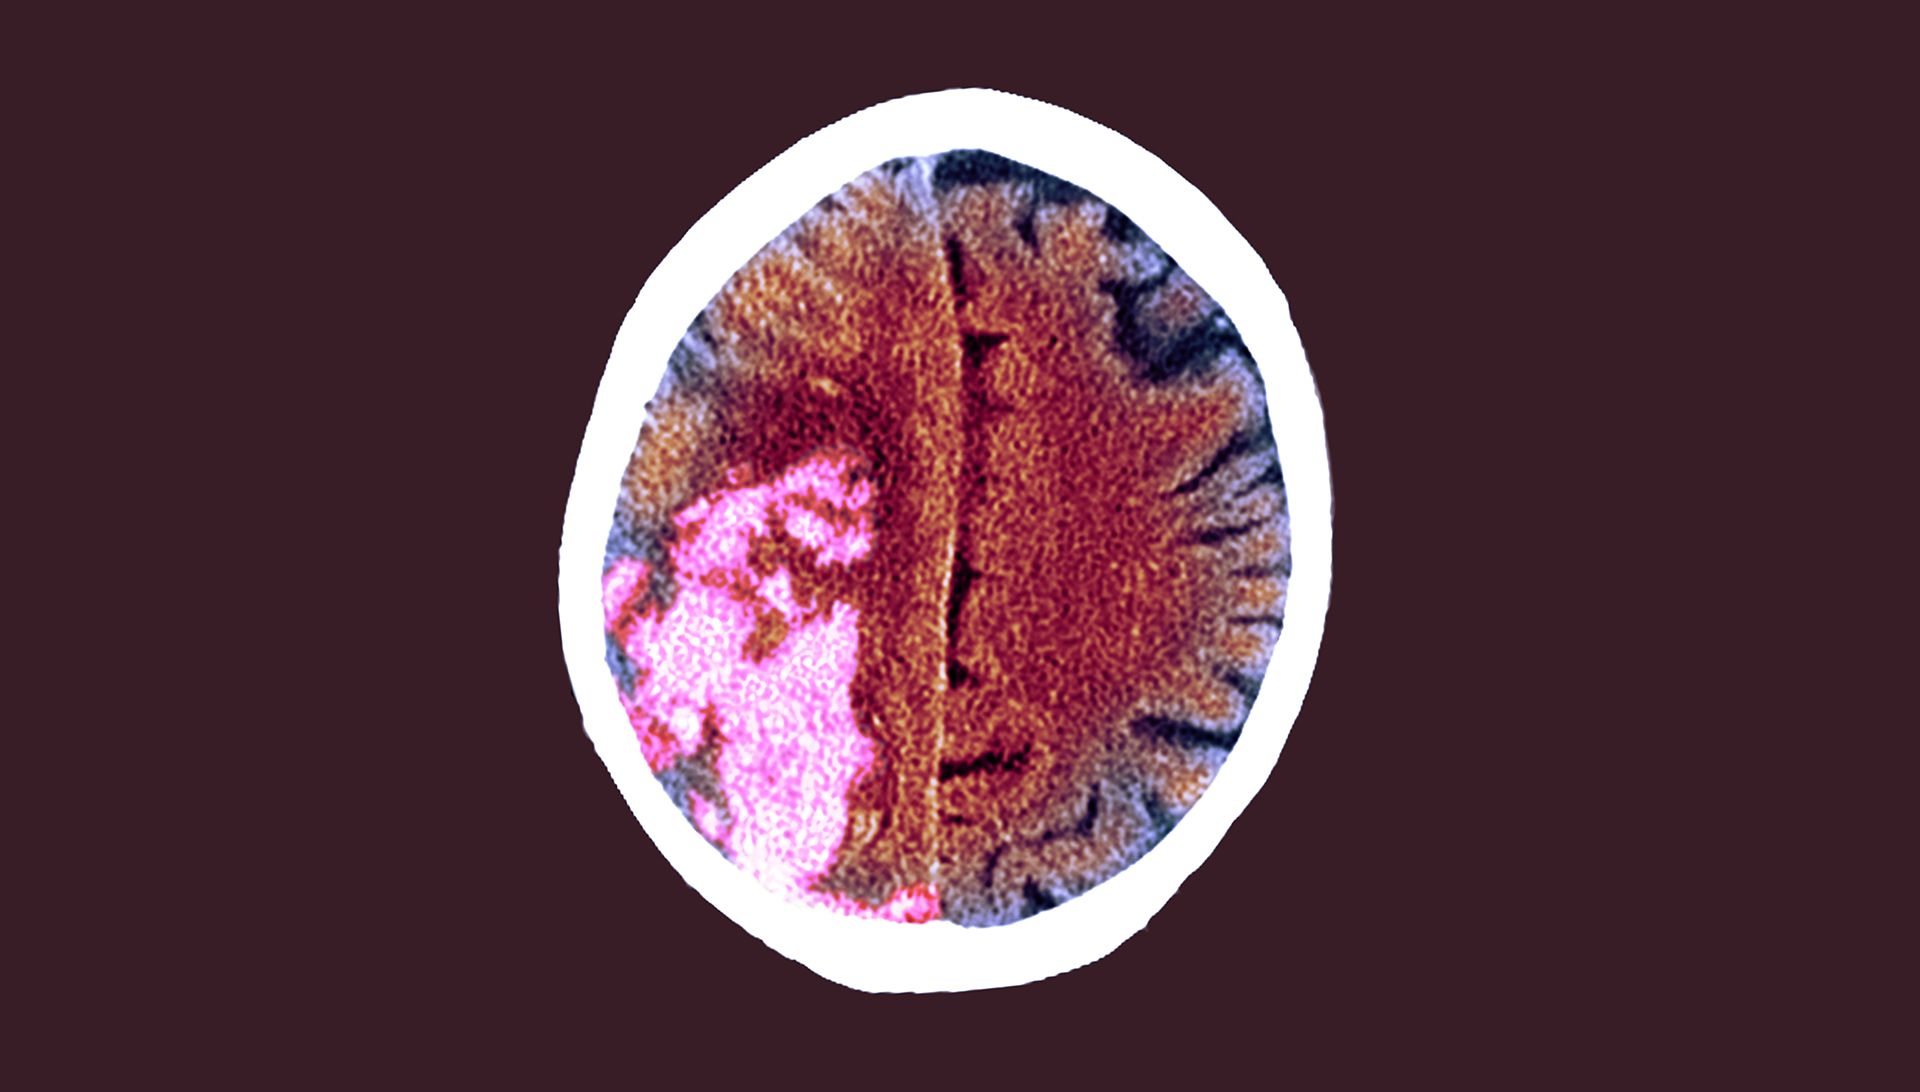

Stroke: clinical review

Dr Roser Icart-Palau and Dr Patrick Gompertz outline the epidemiology, aetiology, diagnosis and management of stroke, in a module updated by Dr Pipin Singh. Key learning points for healthcare professionals include the use of the FAST and ABCD2 scores and the cardinal features of clinical presentations of stroke and transient ischaemic attack.

There are more than 100,000 strokes in the UK each year.1 Scroll within the image below to find out more.

The number of stroke survivors aged 45+ in the UK is expected to rise by 123% in the next 20 years

Around 1 in 5 women will have a stroke in their life

Around 1 in 6 men will have a stroke in their life

The rate of first time strokes in people aged 45+ is expected to increase by 59% in the next 20 years

Recognising stroke is very difficult in the acute phase, but essential if patients are to access emergency treatment within the shortest possible time.

FAST (Face, Arms, Speech, Time) is useful as a first assessment test (see box). Approximately 80% of FAST-positive patients will have a confirmed diagnosis of stroke.2,3

Conditions that mimic stroke and can lead to a positive FAST test without being a stroke including seizures, sepsis, metabolic disorders, functional presentations, demyelinating conditions, migraine and space-occupying lesions (SOLs) of the brain.4,5